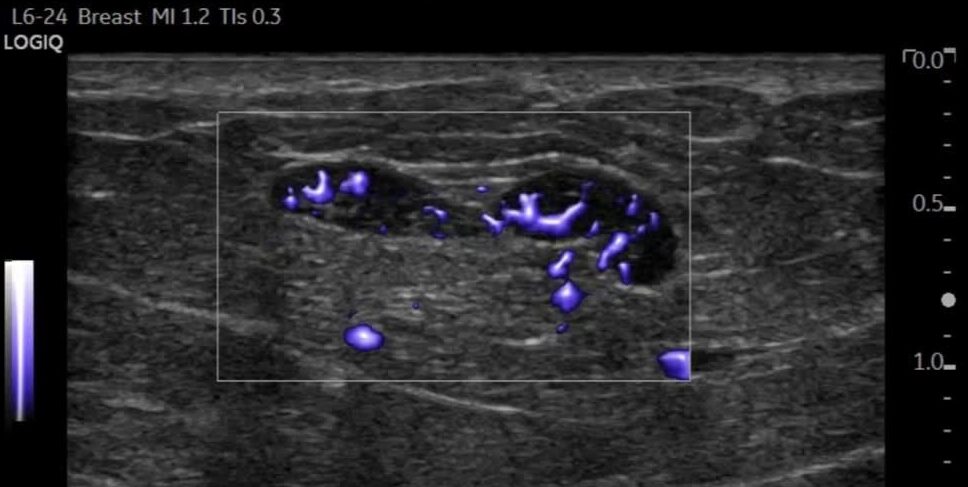

Vascular ultrasound, also known as a duplex study, is a non-invasive test. This test demonstrates to healthcare providers how blood flows through your arms, neck, and legs. High-frequency sound waves create detailed images of soft tissue and blood vessels.

Vascular ultrasound is a non-invasive and remarkably versatile procedure used to examine the circulation in the body’s blood vessels. It can also evaluate arteries or veins in nearly any part of the body, providing a comprehensive understanding of your vascular health.

The technologist places a special probe called a transducer against your skin. You may feel a little pressure as the probe moves over the area. You may hear your blood flowing as it makes a pulsing or whooshing sound, which is a regular part of the examination process.